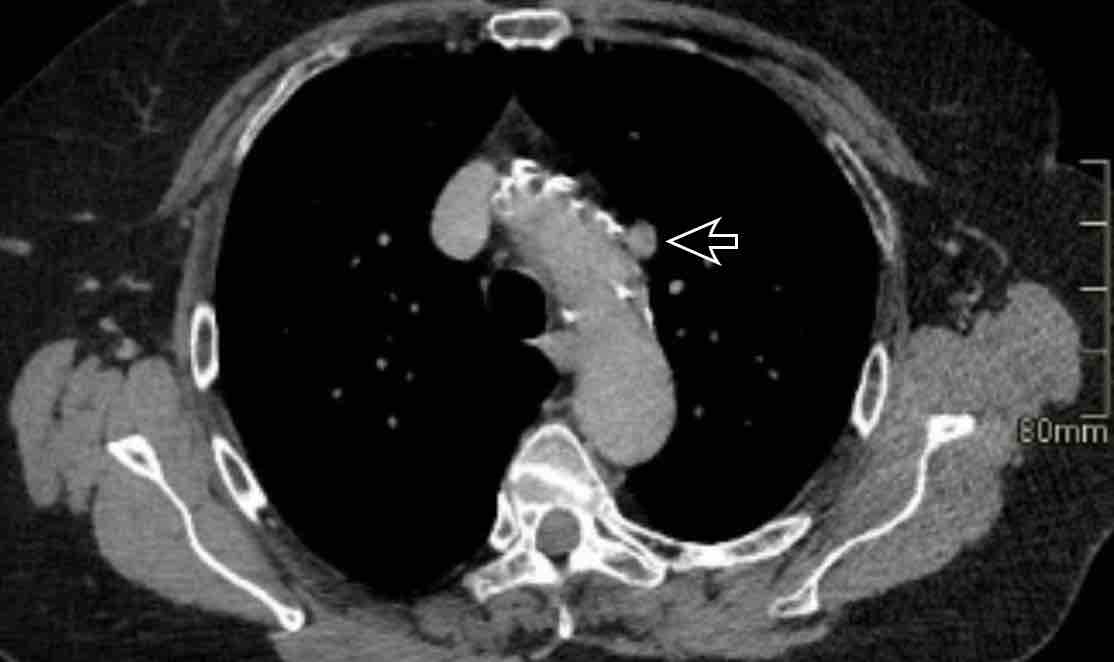

Hình ảnh

Bệnh nhân này được lên kế hoạch cắt thùy trên phải do ung thư phổi và bất thường mạch máu này ban đầu đã bị bỏ sót trên hình ảnh CT.

Những hệ quả trong phẫu thuật của bất thường như vậy nhấn mạnh tầm quan trọng của việc không bỏ sót các biến thể này.

PAPVR bên trái phát hiện tình cờ với dẫn lưu trên tim của máu từ thùy trên trái vào tĩnh mạch tay đầu trái (các mũi tên).